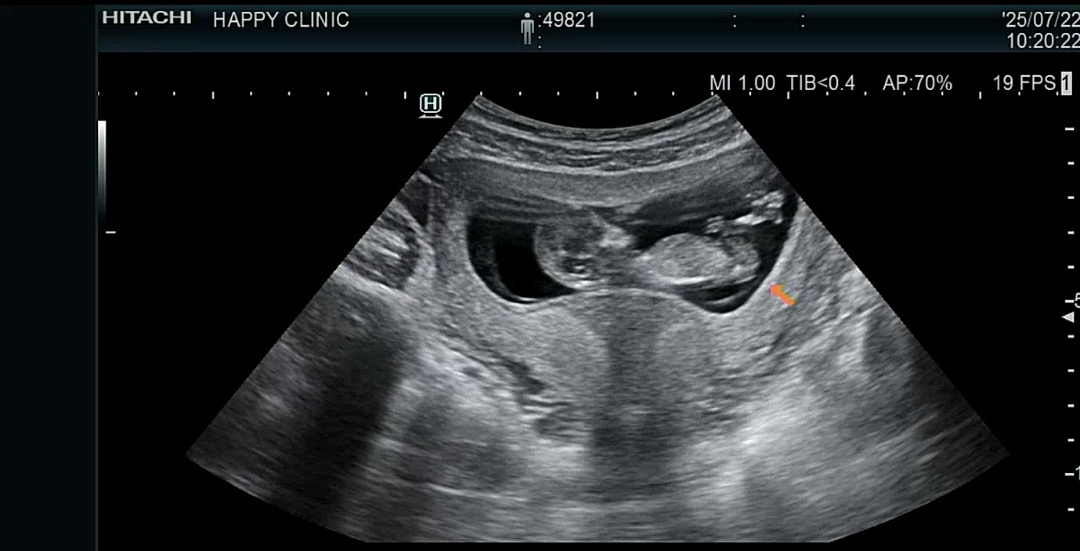

이렇게만 봐선 성별예측 어렵겠죠?

성별확인까지 이제 한달? 남았는데 괜시리 궁금해서 사진만 계속 보는중이네요 ㅋㅋ 12주차엔 다 비슷하게 보인다해서 ... ! ㅋㅋ